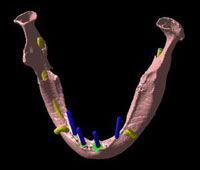

下記の写真をご覧下さい。

これは、吉本歯科医院で実際にインプラント治療(オールオンフォー)が終了した患者さまの顎の状態を3D立体構築画像で見た状態です。

吉本歯科医院でインプラント治療を行う患者さまの顎の状態は、CT画像だけでなくここまで立体化されたものが手術前には手元にあり、シミュレーションを行ってから実際の手術に入るような流れをとっております。

さて、この写真、黄色くうにょうにょとしているのが神経です。

本来骨の厚みがある患者さまの場合は神経の黄色い部分は骨の中に隠れているため3D立体画像で真上から見た場合かくれて見えません。

この方の場合、骨が神経の出口(オトガイ孔)まで磨り減ったためにこのように写ります。

この神経は、ちょっと難しいんですが、下歯槽管(かしそうかん)といい神経、血管が入っているトンネルのような管です。

オトガイ孔はその出口です。

左右片側の下唇および、オトガイ孔の皮膚の知覚を司る神経です。

もし手術であやまってこの神経を損傷すると、下唇およびオトガイ部が麻酔がかかったようにしびれてしまいます。

インプラント手術をしたあと、「顔がしびれだした」といった症状はこの重要な神経に傷をつけてしまったことによって起こります。

この中で、インプラントにおいて執刀する歯科医師が最も留意しなくてはならないのが下歯槽管神経との距離なのです。

インプラント体で下顎骨の中を走る神経やオトガイ孔から出た神経を傷つける可能性があるため手術の前には必ずCT撮影をし、適正な長さのインプラント体の選択が必要となります。

実際にCTで撮影し、「CTデータ3D立体構築画像変換検査」したものがどう見えるのがご覧下さい。CTデータ3D立体構築画像変換検査した場合、3次元でどこにどのようにインプラントを埋め込んでいけばいいのか、立体的に把握することができます。

CTデータ3D立体構築画像変換検査は患者さまの顎の骨や歯の状況を立体的に把握します。あらゆる角度から検討でき、インプラントの植え込み位置、角度などの事前シミュレーションが的確に行われ、数値化することができます。